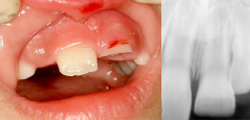

亜脱臼(不完全)、完全脱臼の他、陥入があります。

歯の陥入

治療後